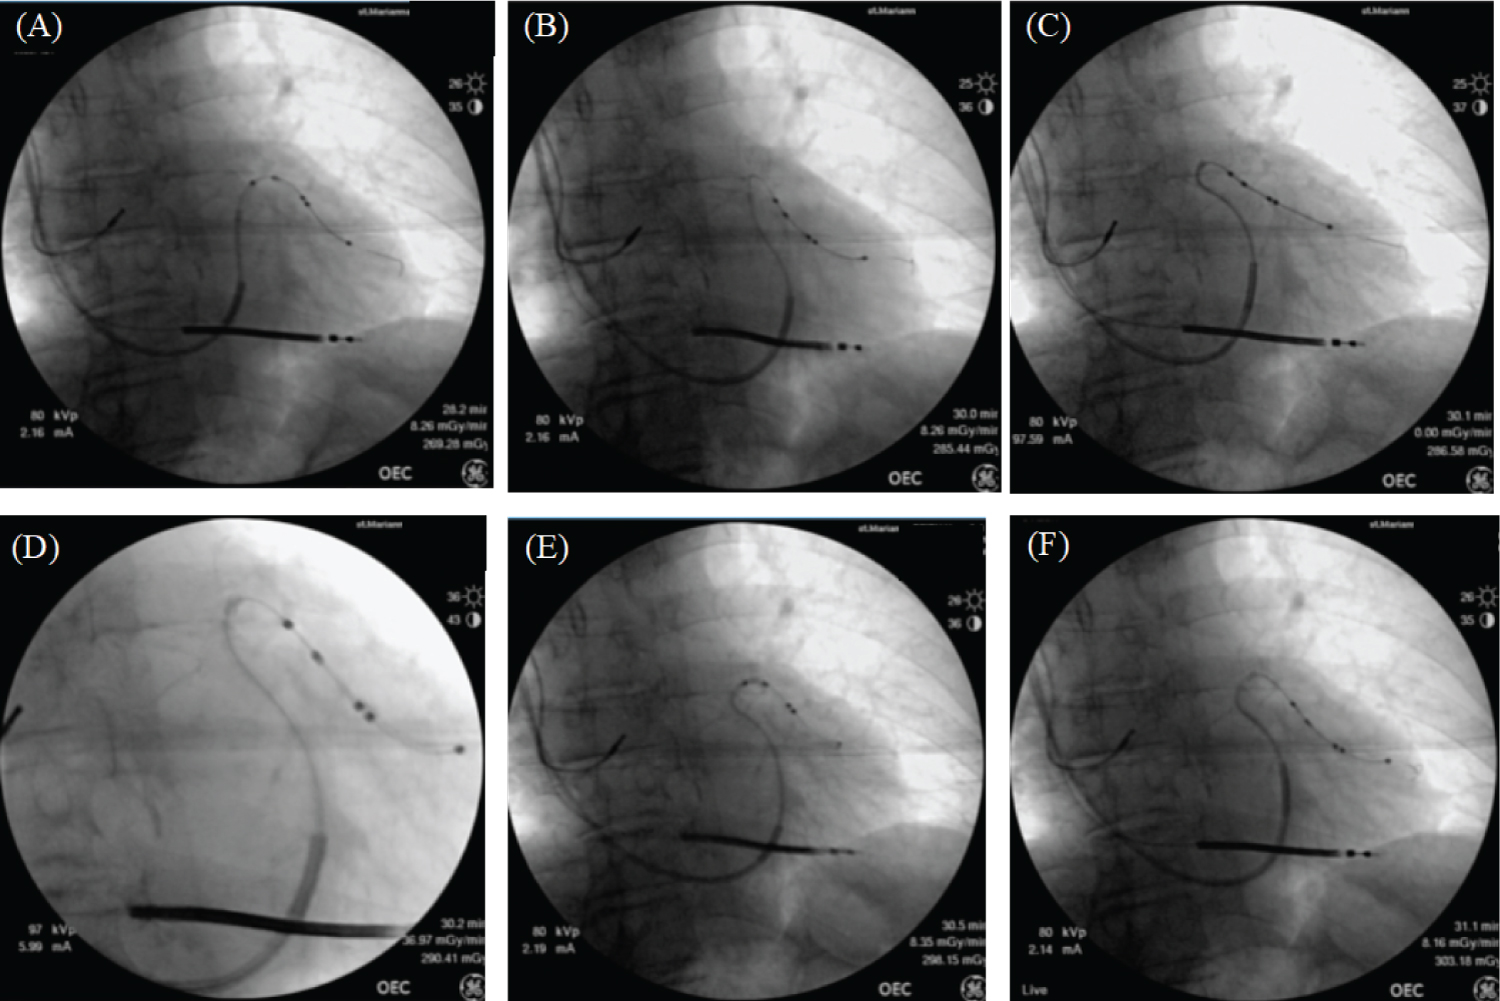

The patient was a CRT-adapted patient and further CRT was performed upon admission. The leads were punctured in the left subclavian vein after creating a left pocket. The CS was cannulated successfully using a CS guiding catheter (Attain Command™ + SureValve™ integrated valve, Medtronic). After inserting the guide catheter into the CS, venography was performed to confirm the same lateral branch of the CS as in the CT. Using a Runthrough NS 0.014-inch peripheral angioplasty wire (TERUMO, Tokyo, Japan) was difficult. We attempted to advance a 90° microcatheter (Attain Select II™ + SureValve™ sub-selection catheter, Medtronic) along with the ASQ lead; however, the microcatheter did not advance over the lateral branch owing to venous tortuosity (Figure 4A, Figure 4B and Figure 4C). We applied a technique using active fixed LV leads, which has already been reported as an anchoring technique [3]. The ASQ lead screw was in the distal segment of the lateral branch (Figure 4D). Next, we attempted to advance a microcatheter by pulling the ASQ lead, and the microcatheter was advanced over the tortuous lateral branch (Figure 4E). Because the ASQ leads are fixed, they do not shift when the ASQ leads are pulled. The ASQ lead was screwed out and led to passing the tortuous lateral branch, and the ASQ lead was finally implanted through it (Figure 4F). Good pacing parameters were obtained without phrenic nerve stimulation. We successfully placed the right ventricular (RV) lead (Sprint Quattro 6935M-55, Medtronic) at the apex of the RV and the right atrial (RA) lead (CapSure Sense 4574-45, Medtronic) in the RA appendage. We connected all leads to the generator (Cobalt XT HF Quad, Medtronic) and closed the pocket. The electrocardiogram after implantation had QRS duration of 104 ms (Figure 2B). Patient follow-up at 6 months postoperatively showed NYHA class 2 with an improvement in EF of 35%, and CRT was continued.

Figure 4: A deeper left ventricular (LV) lead results in deeper positioning of the cannula insertion catheter. Deep engagement of the cannula insertion catheter is obtained without the LV lead coming off. The leads rotate counterclockwise, releasing the fixation mechanism from the venous wall, advancing the LV leads, and helping the LV leads to cross the target site. View Figure 4